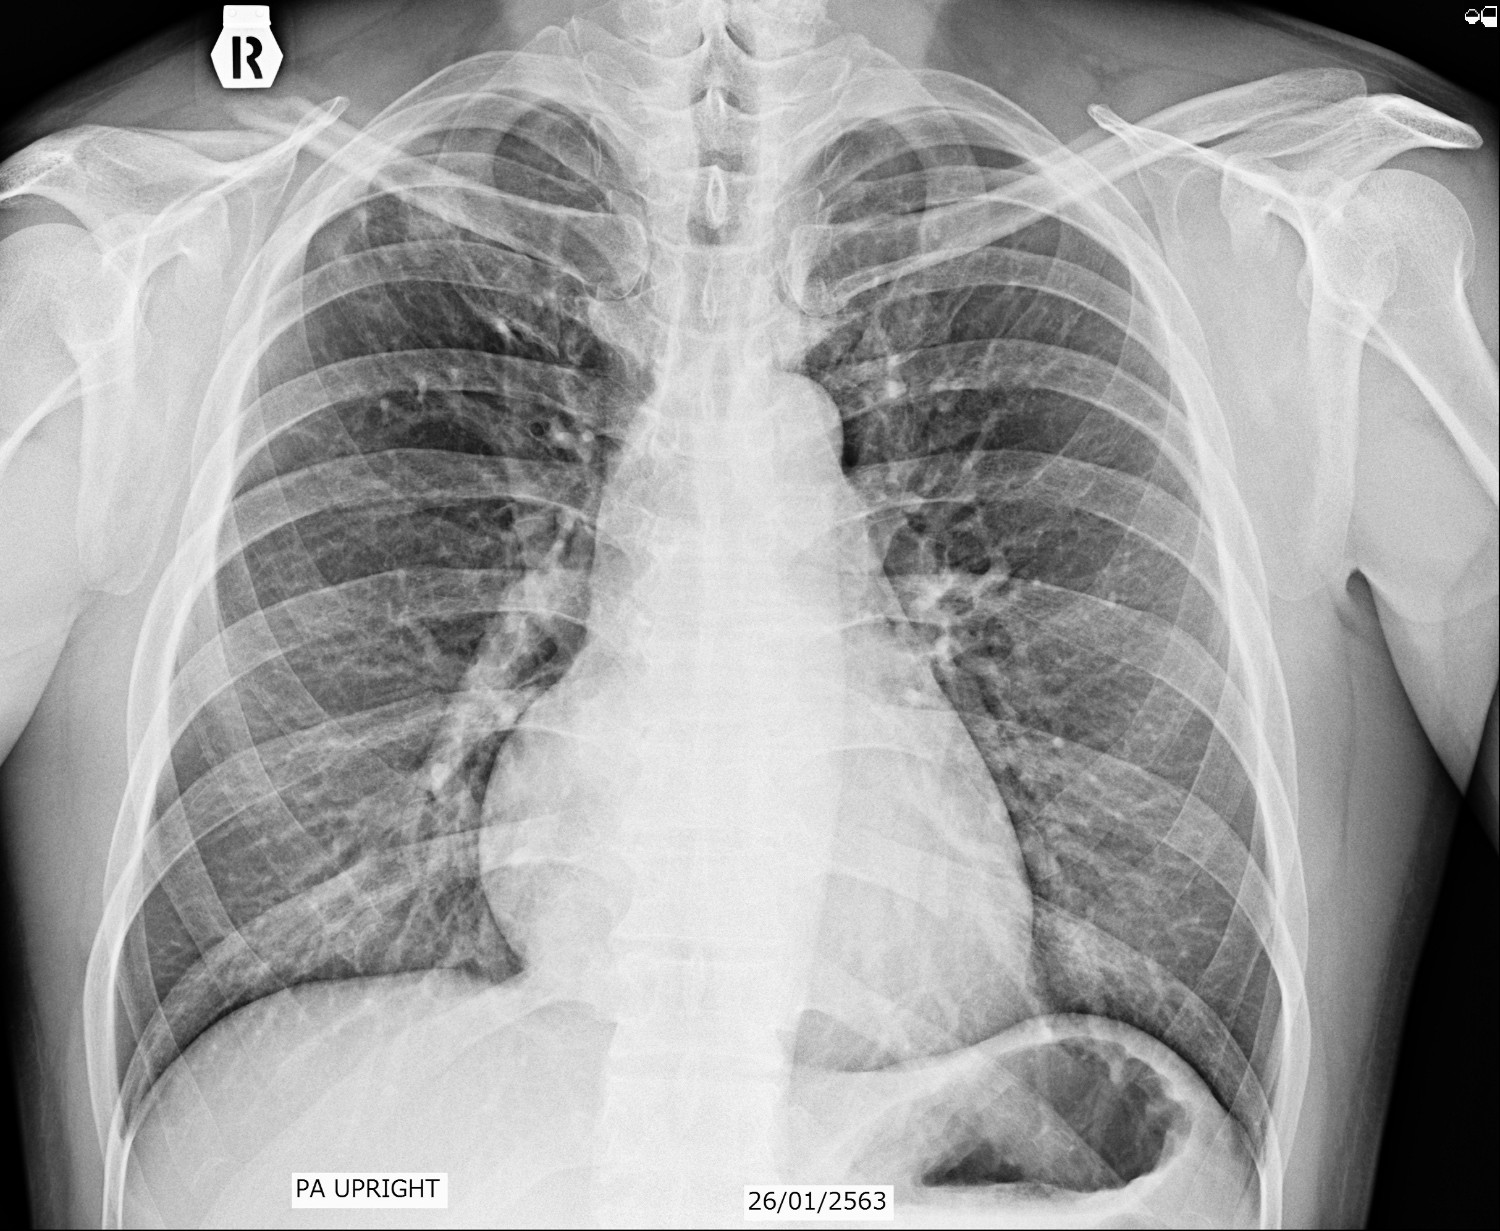

ผมกำลังรักษาตัว TB อยู่ครับ ตั้งแต่ พย 62 ที่ผ่านมาจน ถึงบัจุบัน 24 พค 63 ทานยามมาแล้ว 6 เดือน คุณหมอให้ทานยาต่ออีก 2 เดือนเพื่อความชัวร์

ตรวจเสมหะไม่เคยเจอเชื้อ คุณหมอให้เข้ารับการรักษาเพราะผลฟิลม์ บ่งชี้ชัดเจนครับ ส่วนอาการไอไม่เคยมีเลย

ฟิลม์เรียงวันที่ 26 มค 63,  5 เมษา 63. และ 24 พค 63 ครับผม. กราบขอบพระคุณในความอนุเคราะห์ล่วงหน้าครับผม